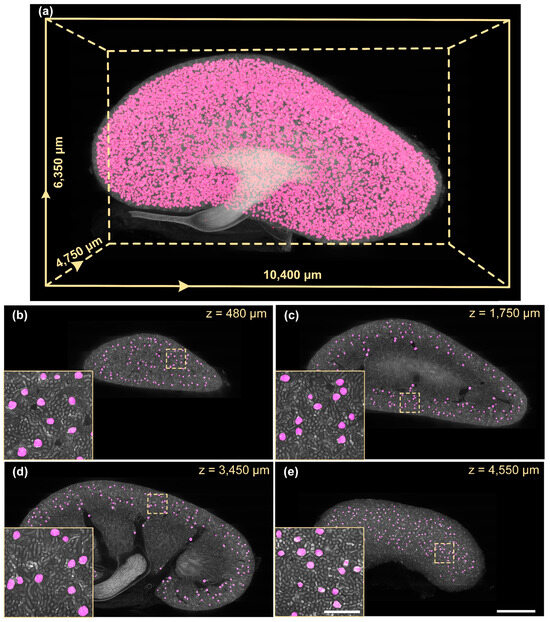

3.3. Quantitative Analysis of Glomerular Development